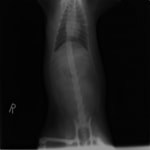

主訴:焼き鳥の竹串を食べたとの事で来院しました。元気・食欲は問題なく、嘔吐などの症状もありませんでした。便にも竹串が1/3程でているとの事でしたが、全ての竹串が出ていないため、内視鏡検査を実施致しました。

内視鏡検査所見:胃内に竹串の先端部分が残っていたため、異物鉗子にて摘出しました。胃内は、全体的に炎症を伴い、出血している部位も確認されました。摘出後は、胃粘膜保護薬・プロトンプインヒビター(胃薬)の内服2剤ならびに食事療法により経過は良好です。

摘出した竹串